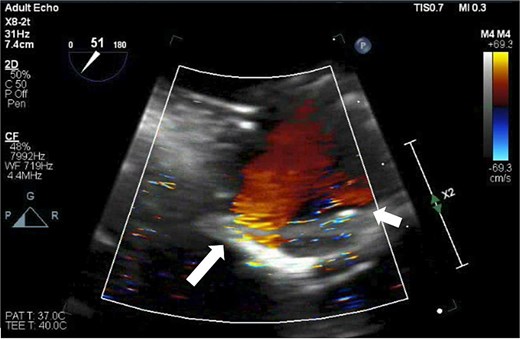

After the aortic cross-clamp was removed, transesophageal echocardiogram (TEE) demonstrated what was suspected to be a mild-to-moderate paravalvular leak along the non/right coronary cusp commissure. The jet appeared highly eccentric and perpendicular to the flow of the left ventricular outflow tract (Fig. 1). Given the size of the leak, it was decided to rearrest the heart. After reopening the aortotomy and assessing the bioprosthesis, no valve defects were seen. But given the suspected friable and thin annular tissue, the base of the aorta was further reapproximated and reinforced to the external sewing ring at the right/noncoronary commissure with multiple prolene, pledgeted sutures. After the second cross-clamp was removed, TEE demonstrated a larger, now broad-based, moderate or greater regurgitant leak at the non/right commissure, and, in addition, the presence of a new mild leak along the left/right commissure (Fig. 2). At this point, a transprosthetic leak was suspected with potential malfunction of the valve. The heart was rearrested for a third time, and the bioprosthetic valve was reexamined and annulus probed. The valve was explanted without any annular pathology being evident, and examination of the valve on the back table demonstrated a torn area of cloth along the right/non and left/right commissures of the cuff at the level of the stent posts, suspected to be the site of the leaks (Fig. 3). A new same-sized 27 mm Inspiris Resilia valve was chosen, and the valve was placed on to the annulus in a supra-annular fashion with multiple ventricularly based 2-0 Ethibond EXCEL pledgeted mattress sutures, and secured with the COR-KNOT device.

TEE showing a leak (arrows) from the Inspiris Resilia valve in the aortic position after the first aortic cross-clamp was removed. (a) Long axis view. (b) Short axis view.